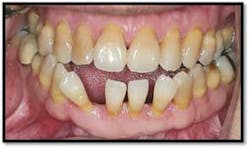

Tissue is light pink, tight and firm. All pockets are 1-3mm, no BOP

LR lingual post Tx and LL lingual post

Tissue is light pink, tight and firm. Pockets 1-3mm no BOP

Charting shows that all pockets are now generalized 1-3 mm with no BOP